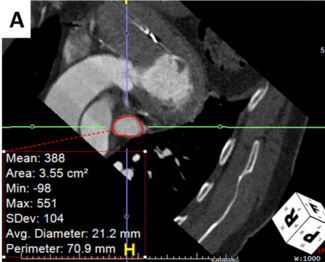

A 70-year-old female was taken up for optical coherence tomography (OCT)-guided percutaneous coronary intervention (PCI) of a calcified left anterior descending artery (LAD).